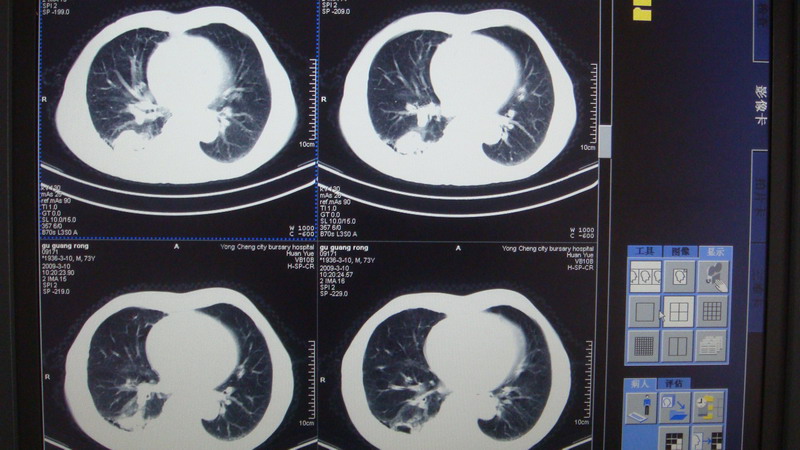

以下是引用光影相伴在2009-3-11 17:27:00的发言:[br]支持 右肺下叶周围型肺癌伴右肺门纵隔淋巴结转移;右上肺继发型肺结核(硬结\\纤维灶);右侧少量胸胸腔积液。另:不排除右侧胸膜转移可能。

以下是引用随光逐影在2009-3-11 16:57:00的发言:[br]支持 右肺下叶周围型肺癌伴右肺门纵隔淋巴结转移;右上肺继发型肺结核(硬结\\纤维灶);右侧少量胸胸腔积液。另:不排除右侧胸膜转移可能。

以下是引用草之原在2009-3-11 19:03:00的发言:[br]支持 右肺下叶周围型肺癌伴右肺门纵隔淋巴结转移;右上肺继发型肺结核(硬结\\纤维灶);右侧少量胸胸腔积液。另:不排除右侧胸膜转移可能。